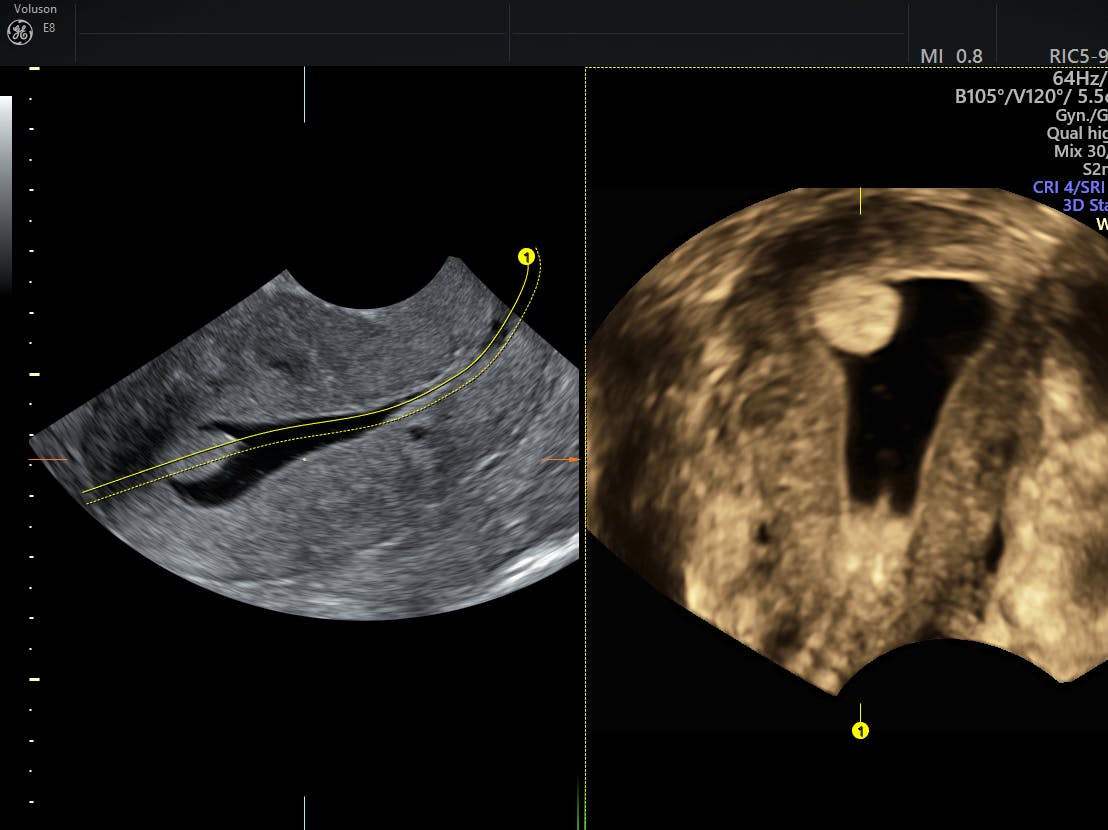

Septate Or Bicornuate Uterus Accuracy Of Three Dimensional Trans

The Role Of Three Dimensional Ultrasound In Gynecology Scitemed